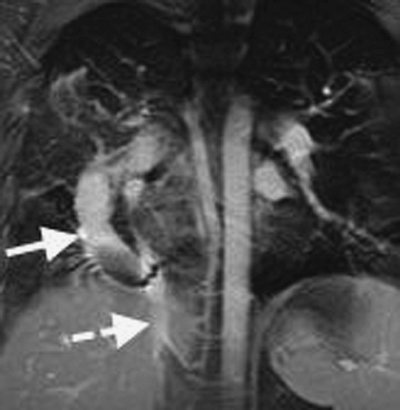

Pulmonary Venolobar Syndrome

Also referred to as the scimitar syndrome or hypogenetic lung syndrome, pulmonary venolobar syndrome is a form of partial anomalous pulmonary venous return that is accompanied by ipsilateral lung hypoplasia. The anomalous venous return is commonly to the inferior vena cava (Fig. 16-5). The hypoplastic lung (which is almost always right sided) is supplied partly or completely by systemic arteries. The ipsilateral pulmonary artery is diminutive. Associated cardiovascular anomalies are frequent, the most common being atrial septal defect (6). Other associated anomalies include pulmonary sequestration, absence of the inferior vena cava, and accessory diaphragm. Less commonly, the syndrome may involve tracheal trifurcation, eventration and partial absence of the diaphragm, phrenic cyst, horseshoe lung, anomalous superior vena cava, and absence of the left pericardium (7). Bronchial anomalies are common, particularly isomerism (identical right and left branching patterns). The anomalous vein is usually visible on frontal chest radiographs as a broad, gently curved shadow descending to the diaphragm just to the right of the heart (Figs. 16-6 and 16-7). The shadow is shaped like a Turkish sword (a scimitar); thus, the designation scimitar syndrome. Other radiographic findings include a small ipsilateral hemithorax with diminished pulmonary vascularity, shift of the mediastinum toward the involved side, and, often, indistinctness of the cardiomediastinal border on the involved side. The lateral radiograph usually

FIGURE 16-5. Pulmonary venolobar syndrome. MRI of a 24-year-old man shows a large venous structure (solid arrow) draining into the abdominal inferior vena cava (dashed arrow).